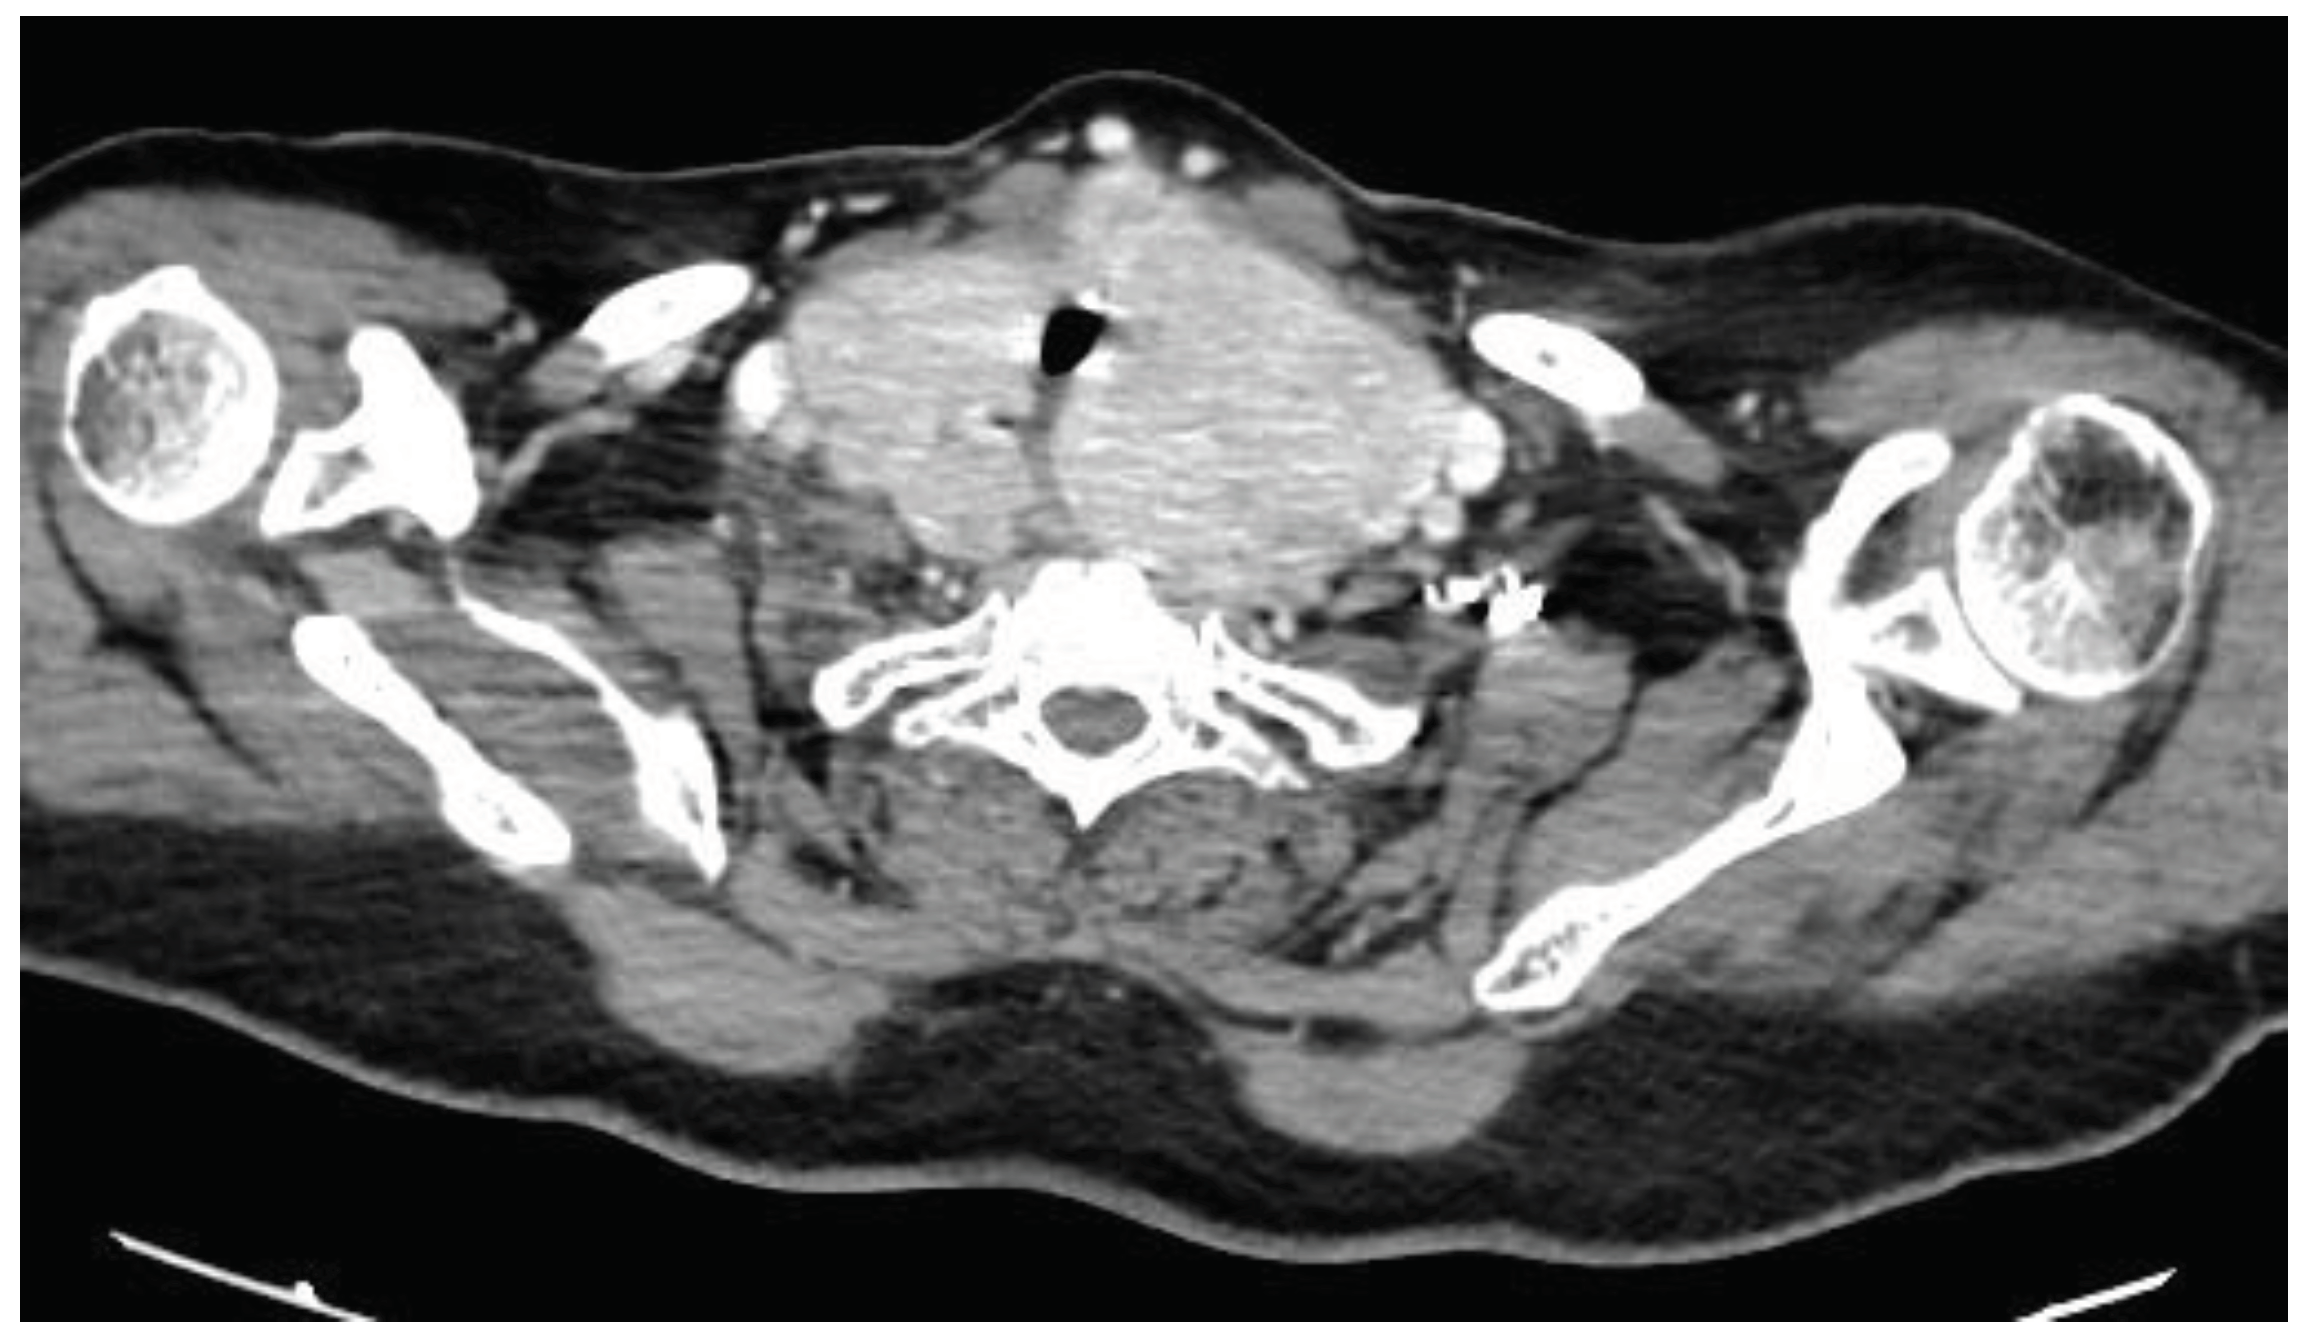

The physical examination revealed that the patient measured 149 cm in height and weighed 84 kg, resulting in a BMI of 37.8 kg/m2. Her neck circumference was measured at 49 cm. Upper airway assessment indicated a mallampati score of 4, and a large goiter was clinically evident, with no craniofacial abnormalities observed. The lower edge of the thyroid gland was not palpable during the examination. However, a computed tomography (CT) scan of the neck and thoracic inlet had previously confirmed a multinodular enlargement of the thyroid gland, with retrovascular extension and compression of the trachea (Figure 1).

Figure 1. Computed tomography (CT) scan at the level of the thoracic inlet showing enlargement of the thyroid gland with locoregional extension and signs of compression.